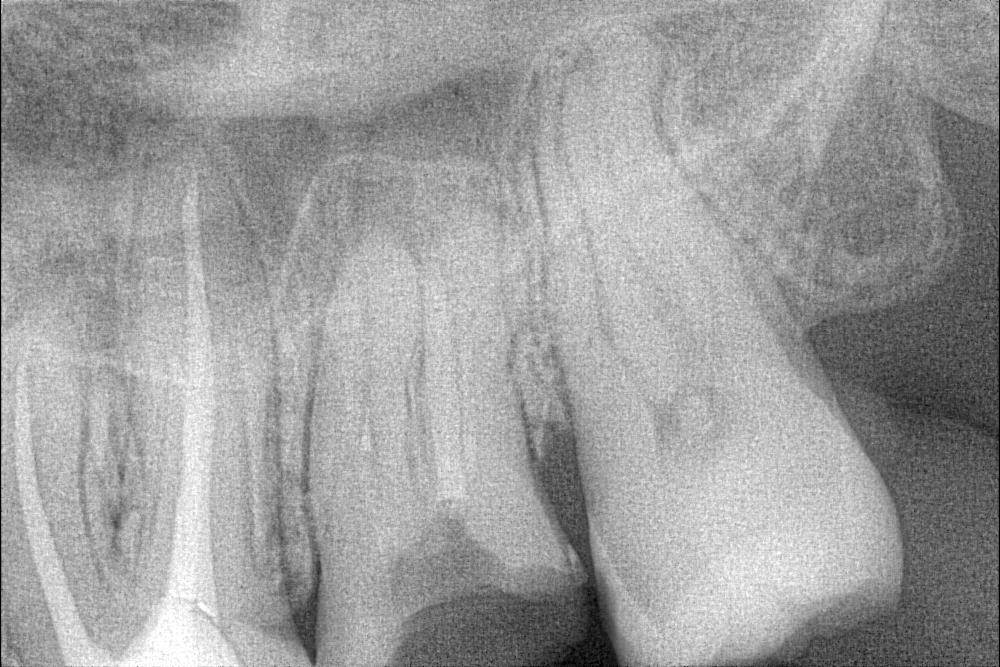

NinaAnn Опубликовано 14 апреля, 2023 Поделиться Опубликовано 14 апреля, 2023 Все требуют 3д снимки, что бы только сказать подлежит ли 7 восстановлению. Можно ли по ренгену хоть что то прояснить. Залечили 8й зуб 7 разрушен, 8 отвалилась стенка зуба. Делать 3 д перед диагнозом, потом если имплантация, снова 3д 1000 мкз тоже не просто снимок. 1й снимок месяц назад. 2й сегодня. Может просто снимок участка ренген что то поможет прояснитью Ссылка на комментарий

NinaAnn Опубликовано 15 апреля, 2023 Автор Поделиться Опубликовано 15 апреля, 2023 По ренгенам, говорят, о возможной кисте и воспалении. Импоантируют же в здоровую ткань. И 3 д снимок перед имплантацией после удаления и заживления. А это больше месяца. Не совсем понимаю что не потребуется ещё снимок. К тому же 6 тоже разрушен. А 8 единственный был живой но его залечили, именно залечили, громадная пломба. Может кто подскажет ещё тактику. У всех своя специализация, и на каждом этапе спецу свои данные. Ссылка на комментарий

Carioznik Опубликовано 17 апреля, 2023 Поделиться Опубликовано 17 апреля, 2023 (изменено) 1 час назад, NinaAnn сказал: о,1 милизиверт нагрузка. Это 10000 микрозиверт. Как я поняла Это 100 микрозиверт 1 час назад, NinaAnn сказал: почему эдодонтия это сразу томография? Далеко не всегда. Но повторная эндодонтия (перелечивание, как у Вас) - это сложное, долгое, дорогое и труднопредсказуемое лечение, да ещё и требующее в дальнейшем закрытия зуба искусственной коронкой. Поэтому, чтобы определить прогноз лечения зуба, выявить подводные камни с которыми можно столкнуться а процессе лечения - лучше сделать КТ. Можно и без КТ попробовать перелечить зуб, но повышается риск ошибки в диагностике. (Например, Вы потратили много времени, сил и финансов на этот зуб, сделали на него коронку, а через 1-2года его всё равно пришлось удалить). Пример: если Вы готовы пртратится на этот зуб и вероятно удалить его в течении 1 года - делайте без КТ. Ps: КТ, конечно не панацея, и не даст 100 процентного результата, но может оказаться весомым фактором для принятия, более-менее, правильного решения Изменено 17 апреля, 2023 пользователем Carioznik Ссылка на комментарий

Гарриевич Опубликовано 17 апреля, 2023 Поделиться Опубликовано 17 апреля, 2023 По рекомендации европейской ассоциации эндодонтии при перелечивании хотя бы 1 зуба КЛКТ строго рекомендовано Ссылка на комментарий